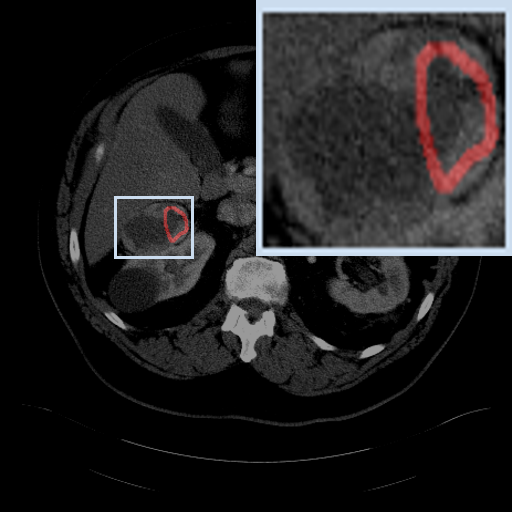

Figure 3: Qualitative comparison visualization of DEAP-3DSAM and baselines on four datasets.

IV-B2 Qualitative Performance Comparison

We also performed qualitative analysis on four datasets. As illustrated in Fig. 3, DEAP-3DSAM accurately identifies the target regions and closely matches their size. In contrast, 3DSAM-Adapter [3dsamadapter] exhibits limitations in matching the size and shape of the target regions. This proves that DEAP-3DSAM captures more complex image features, owing to its Dual Attention Prompter and Feature Enhanced Decoder. Furthermore, while these SAM-based methods are nearly capable of localizing the target regions, many traditional methods, i.e. UNETR++ [unetr++], Swin-UNETR [swinunetr], and TransBTS [transbts], struggle to achieve this. This highlights the potential of SAM-based methods for addressing complex 3D segmentation tasks.